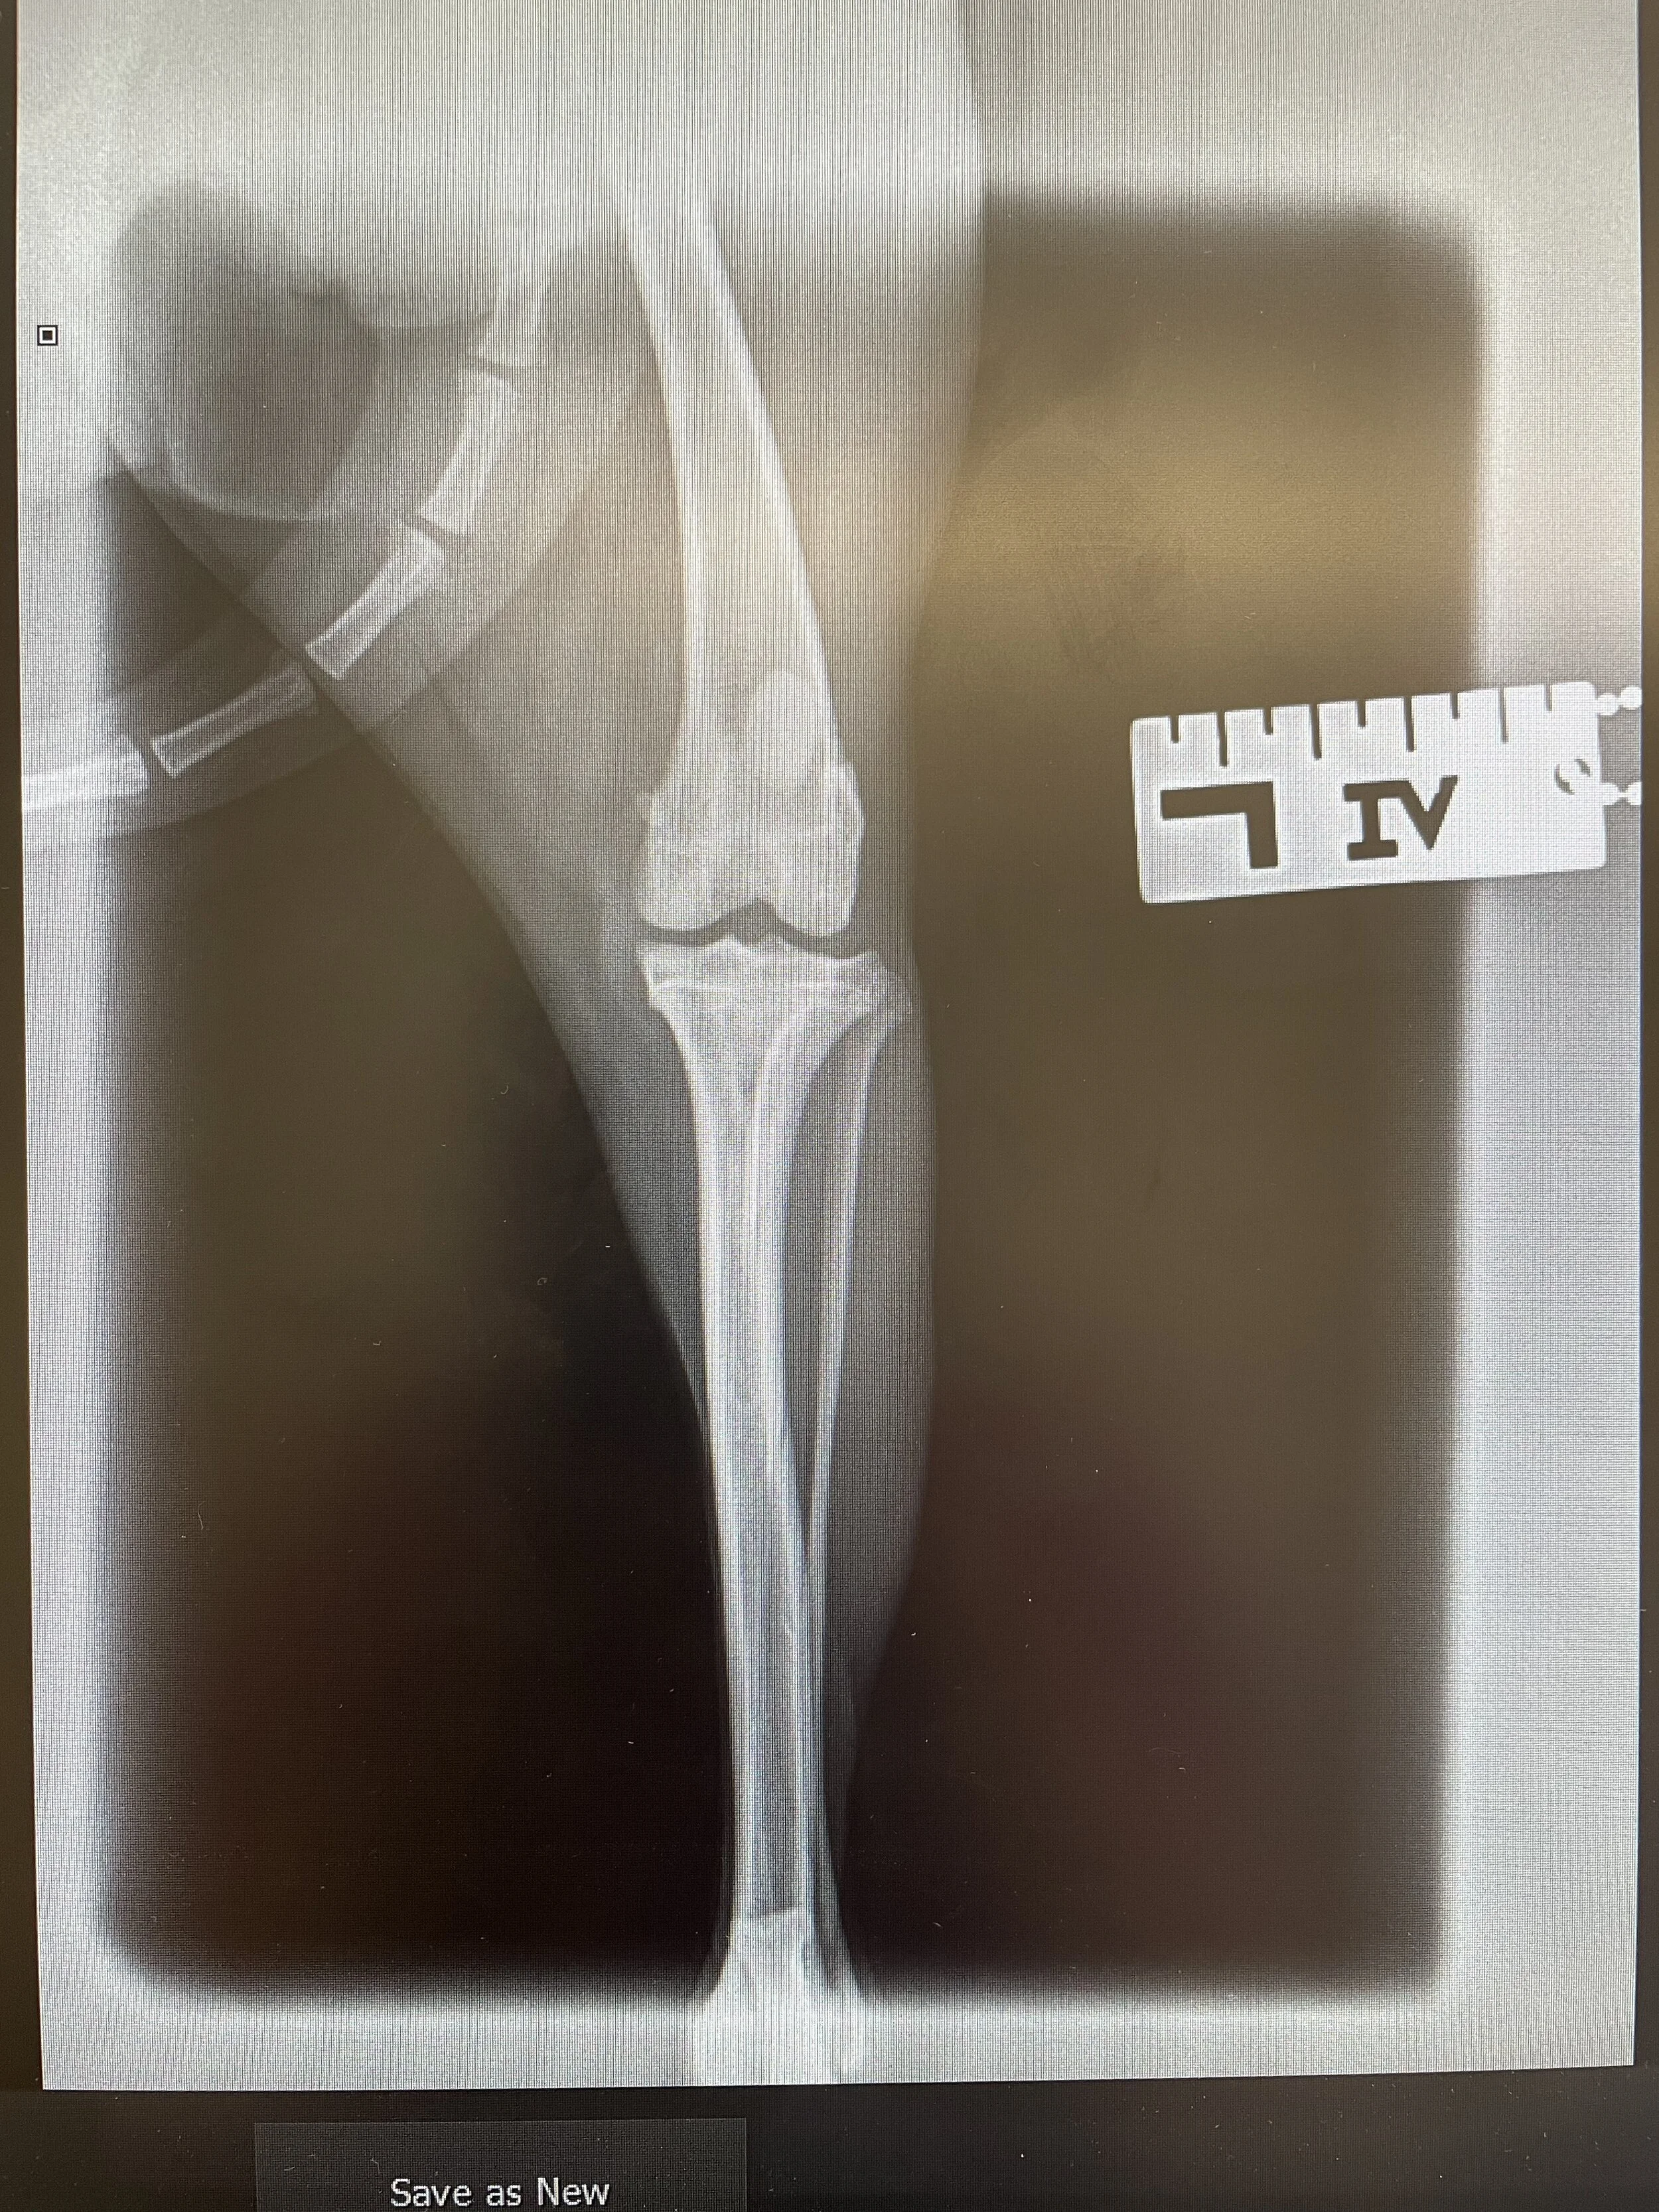

This is the before surgery X-ray (Image: Coquet Vets, 2021)

Multiple X-rays were taken. We took two views of each leg, a lateral position, which is the patient lying on the right or left side, as well as a view called ‘dorso-ventral’, which is the patient lying on their front and we stretch the leg out backwards. The X-ray head is positioned over the area that we want to X-ray (in this case the stifle and hips).

We sent all of the X-rays to Neil Adams, our visiting orthopaedic surgeon. He has been doing orthopaedic surgeries for fifteen years. Neil advised that Bella needed surgery, and he recommended operating on the worst leg (left) first, but that it was likely she will need to have both legs operated on. Luxating patella’s don’t always need surgical treatment, but due to the frequency of Bella’s luxation, surgery was indicated.

After speaking to Neil, a date was confirmed to go ahead with patella surgery on the left leg. Neil performed the surgery by deepening the trochlear groove (the patella sits in this) and performed a tibial tuberosity transposition. This is corrective surgery to secure the patella into the trochlear groove. This was stabilised with wires and then the wound was sutured closed. We always take post-operative X-rays to confirm the wire is in the correct place.